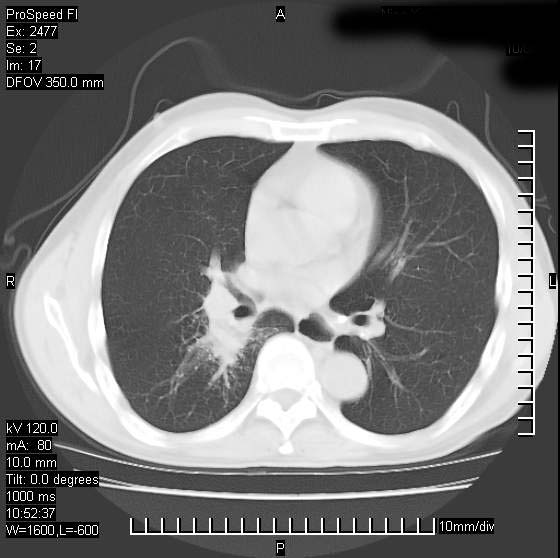

以下是引用天南地北在2007-10-9 14:29:00的发言:[br]1:右上肺结核[br]2:右肺下叶肿块:不支持肺癌,首先考虑炎性病变-肺脓疡可能性大[br]理由:1:临床病史支持,肺脓肿症状不明显应该是不规则服药造成。[br] 2:肿块边缘模糊,周围可见炎性渗出,长毛刺,内见支气管征,不过有点不规则。[br] 我感觉下肺癌这个诊断有点偏左,建议积极抗炎治疗后复查

以下是引用卜一在2007-10-9 15:55:00的发言:[br][br] [br] 1:右上肺结核[br]2:右肺下叶肿块:不支持肺癌,首先考虑炎性病变-肺脓疡可能性大[br]理由:1:临床病史支持,肺脓肿症状不明显应该是不规则服药造成。[br] 2:肿块边缘模糊,周围可见炎性渗出,长毛刺,内见空气支气管征,不过有点不规则。[br] 我感觉下肺癌这个诊断有点偏左,建议积极抗炎治疗后复查![br]支持! [br] [br] [br]

以下是引用wxy7406在2007-10-9 21:02:00的发言:[br]结合临床病史首先考虑感染性病变,但周围型肺癌不能除外,1.患者年龄偏大2.临床有咯血3.(也觉得是最重要的一点)病灶内有偏心性空洞。

以下是引用王仕学在2007-10-9 13:48:00的发言:[br]右下肺周围性肺癌可能性大,最好活检吧

以下是引用hhcckk在2007-10-9 15:18:00的发言:[br]右上肺病灶考虑结核,病灶多种形态并存(纤维化、增殖性病灶并存)[br]右下肺病灶比较难说,个人意见更趋向于“天南地北”的诊断----肺脓肿[br]1、病人有明显的寒战,高热,肿瘤病人很少出现[br]2、病灶周围的肺纹理走向柔和,没有肿瘤病灶常见的集束征[br]3、病灶边缘的毛刺较长,恶性肿瘤多为短毛刺[br]痰中血丝和病人的年龄是两个不利于良性肿块的因素,建议早点活检

以下是引用ydx_74在2007-10-9 15:53:00的发言:[br]右上肺结核,右下中心性肺癌可能大,肺门淋巴结肿大。